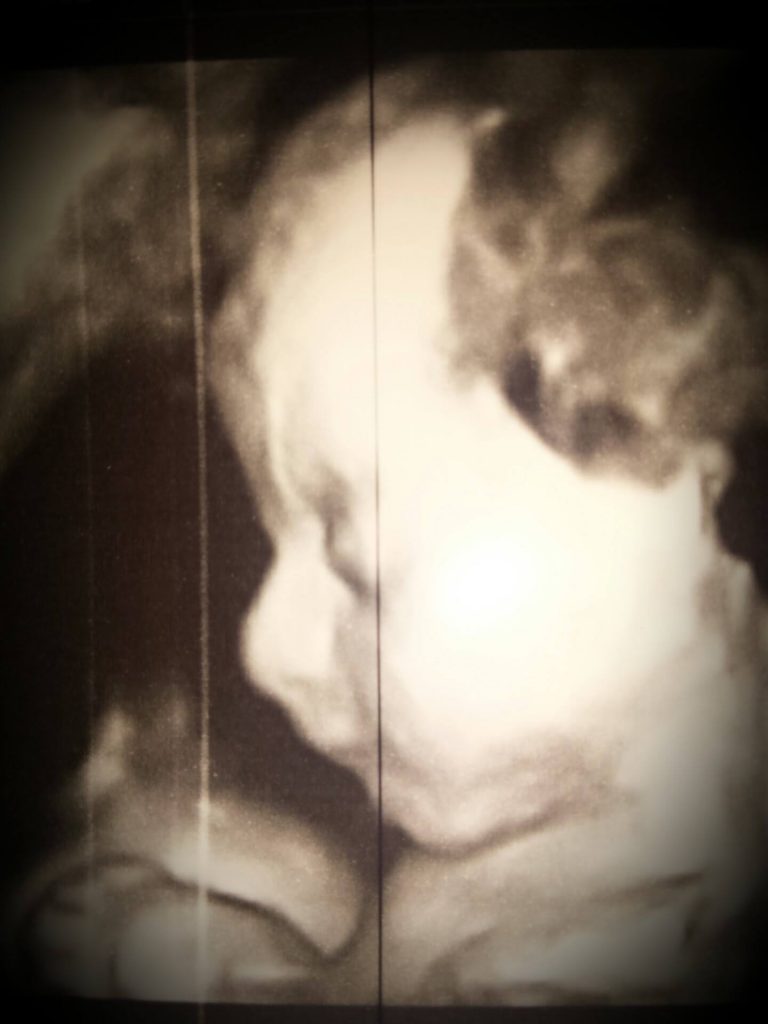

Apoi la 38 de saptamani prin operatie de cezariana a aparut minunea noastra: Alexia-Elena pe 5 Martie 2016 la ora 10:50 cu nota 9, 51 cm si 3,300 g. Am fost cei mai fericiti!!!!! Am trecut prin multe dar Dumnezeu a vrut ca printesa noastra sa vina pe aceasta lume. A iesit un copil minunat, dulce si perfect.”

Foto: Arhiva personala Anca Oloieri